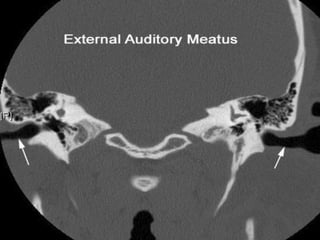

• External

• Middle

• Inner